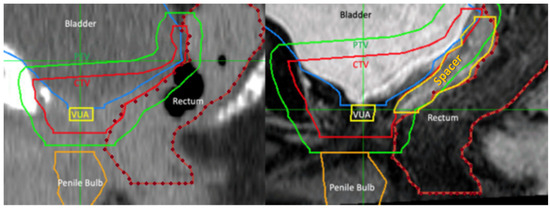

Patients underwent rectal spacing with either hyaluronic acid (Barrigel®, Palette Life Sciences, Santa Barbara, CA, USA) or hydrogel (SpaceOAR®, Boston Scientific, Massachusetts, Marlborough, MA, USA). The insertion technique is demonstrated in Figure 1. The rectal spacer was inserted into the perirectal fat posterior to the retained Denonvillier’s fascia between the bladder and anterior rectal wall using a transperineal approach under TRUS guidance. An indwelling urinary catheter was inserted to help delineate the vesico-urethral anastomosis (VUA). The perirectal fat was identified between the bladder and anterior rectum. An 18G spinal needle (Quincke Type Point® Spinal Needle, BD, Stockholm, Sweden) was inserted using a freehand technique targeting the midline of the prostate bed under sagittal TRUS guidance. Hydrodissection of the perirectal fat in the sagittal midline with 3 to 5 mL of sterile saline was attempted and, if successful, followed by insertion of 6 to 9 mL of hyaluronic acid (66% of cases) or hydrogel. After insertion, the vesico-rectal separation was calculated by measurement at the midline of spacer’s sagittal length. Pre- and post-spacer insertion images can be seen in Figure 2.

Figure 2.

Pre- and post-spacer insertion MRI images (sagittal) with hyaluronic acid in perirectal space extending just above pelvic floor.